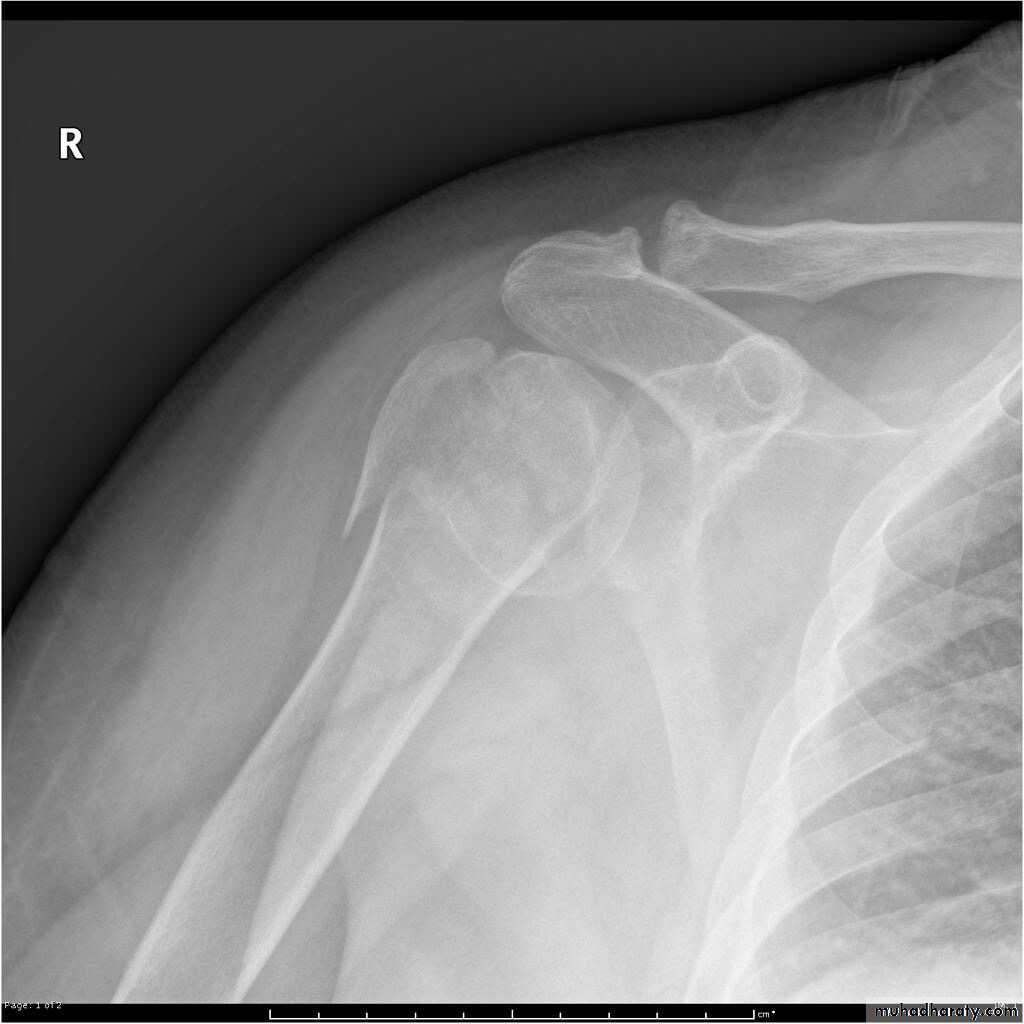

X RAY

27

28